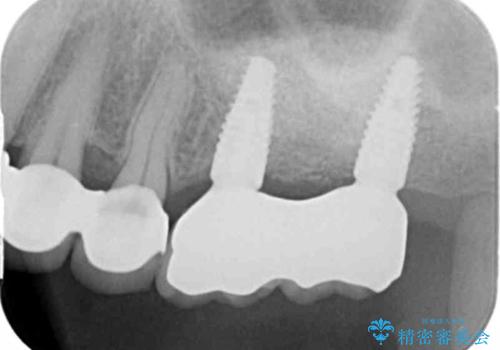

治療前X線写真の歯の周囲黒くなった部分は骨が溶けてしまった部分です。

このような場合インプラント治療を計画するにはまず吸収した骨を再建・造成しインプラントを埋め入れることが可能な状態にすることが先決となります。

今回は、高度に骨の吸収が見られたためチタンメッシュを用い大幅な骨の造成を行い、インプラント周囲に幅・高さとも長期的な予後が見込める十分な骨が再建されました。